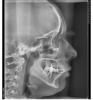

Девчат, а тут нет случайно Лора? Посмотреть рентгеновские снимки, на наличие гайморита) а то описание только завтра, а прием врача послезавтра)

@katerina999, какая интересная конструкция на верхней шестерке 🤔

@katerina999, у вас имплантат сообщается с пазухой, это может стать причиной гайморита в дальнейшем.

Так там видно пазухи мутные-гайморит,тёмные все хорошо